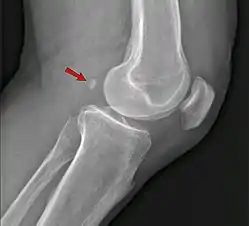

Neck

Shoulder

• An os acromiale forms when any of its four ossification centers fail to fuse. These four ossification centers are called (from tip to base) pre-acromion, meso-acromion, meta-acromion, and basi-acromion. In most cases, the first three fuse at 15–18 years, whereas the base part fuses to the scapular spine at 12 years. Such failure to fuse occurs in between 1% and 15% of cases.[23][24] It rarely causes pain.